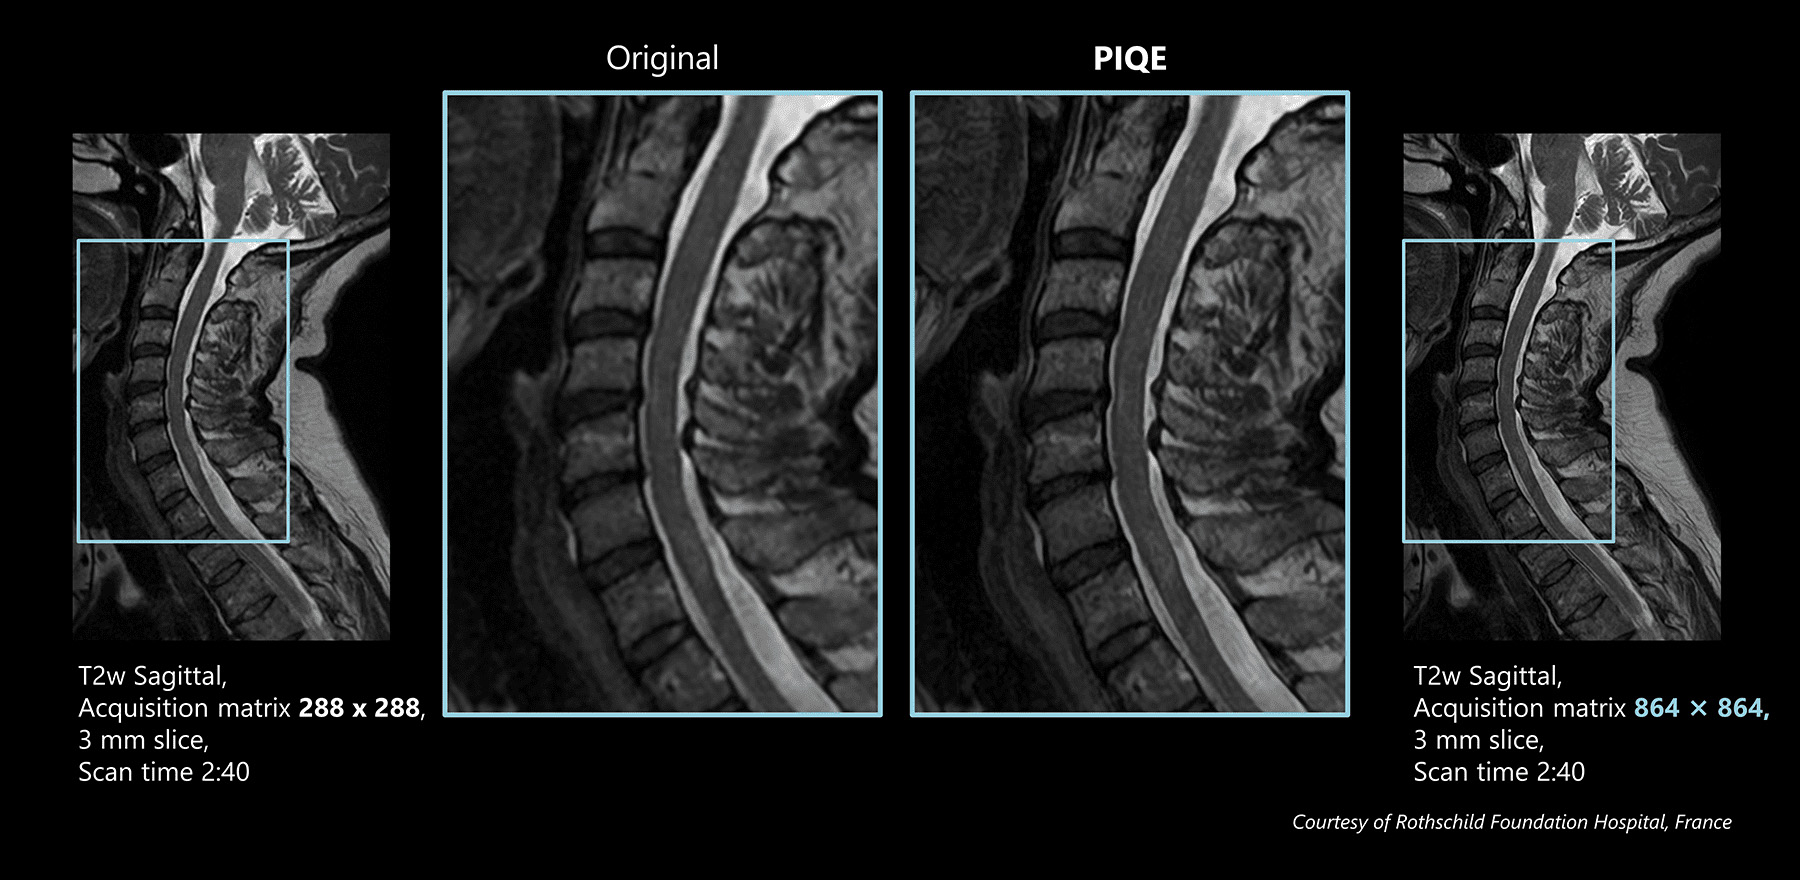

Sagittal T2w for c spin

The original image is a 288 matrix with a 3 mm slice thickness and relatively low resolution, resulting in high SNR.

PIQE reconstruction can acquire high quality images within acceptable scan times.